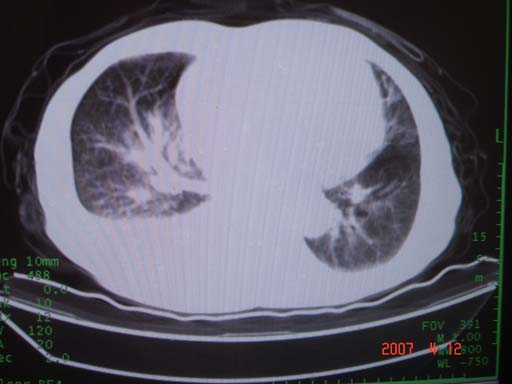

帮我 看看。男77岁咳嗽咯血2月发热2周!病人一般情况可 口痰为鲜红,有点象洗肉水(我看见他吐的痰了)

病灶局限在右肺中上叶,呈大片状实变影,内见空气支气管征,支气管分支较柔软,纵隔内未见肿大淋巴结.支持:感染性病变_1 大叶性肺炎.2 干酪性肺炎.

优先考虑右上肺干酪性肺炎并同侧中叶播散、胸腔积液。分析:右膈肌未见升高、纵隔未见明显右移,胸部各组淋巴结未见可疑肿大,中叶可见支气管铸形,肺野、肺门未见可确定肿块。

单从影像学上来看,该病人应首先考虑,右上肺感染(干酪性肺炎可能大)伴有右侧胸腔积液,理由如下:

1.病灶整体成宽基底征,而未见块状影

2.病灶内的透光区并不是含气支气管征,而像是坏死的肺组织后形成的

3.无肺不张的表现

4.纵隔那未见明显肿大淋巴结

有点象洗肉水的痰,其来源应当是实变引起的血细胞渗出导致,可见支气管气象,实变区有虫蚀状空洞,有明显胸腔积液,未见明显肺门区肿块影,考虑继发型肺结核,干酪性肺炎

右肺上叶实变,实变范围如此之大,如果用肺癌解释的化,应该是比较大的支气管开口发生完全阻塞,但观察上叶前后段支气管还是比较通畅,所以应考虑感染性病变,大叶性肺炎可能,建议抗炎治疗后复查。